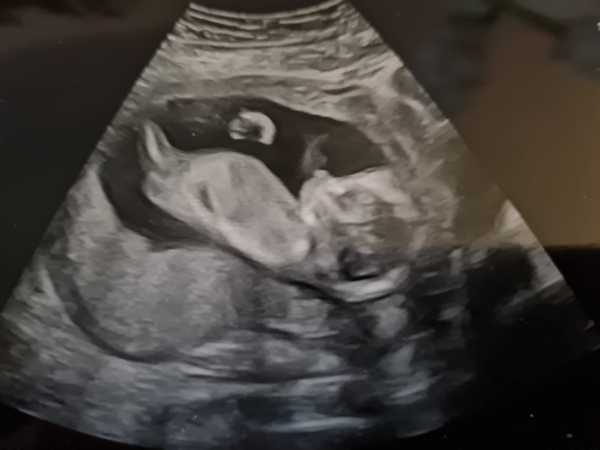

I had a private scan yesterday, everything was good! Told more of our family afterwards. We're getting excited now and I've started buying little bits. Eeeeek. The baby wouldn't stay still for a picture so it's a bit blurry! It also kept drinking and at one point looked straight at us and it was so creepy!! Lol oh and we heard the heartbeat for the first time. Amazing!! Also measuring right on, 15 weeks 4 days.

Lovely lovely pic @HalGem99! So pleased to hear your baby is doing well. :-)